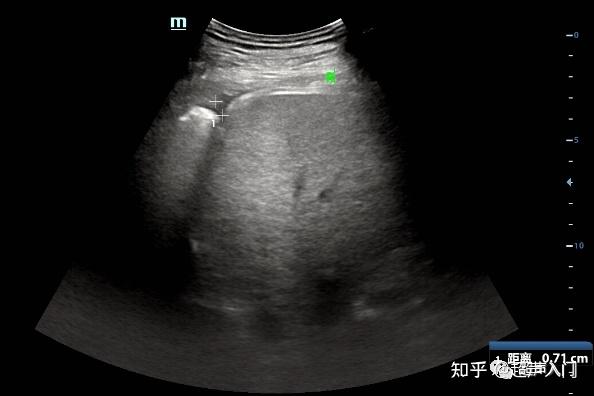

超声微课堂胸腔积液的超声测量

图片尺寸640x478